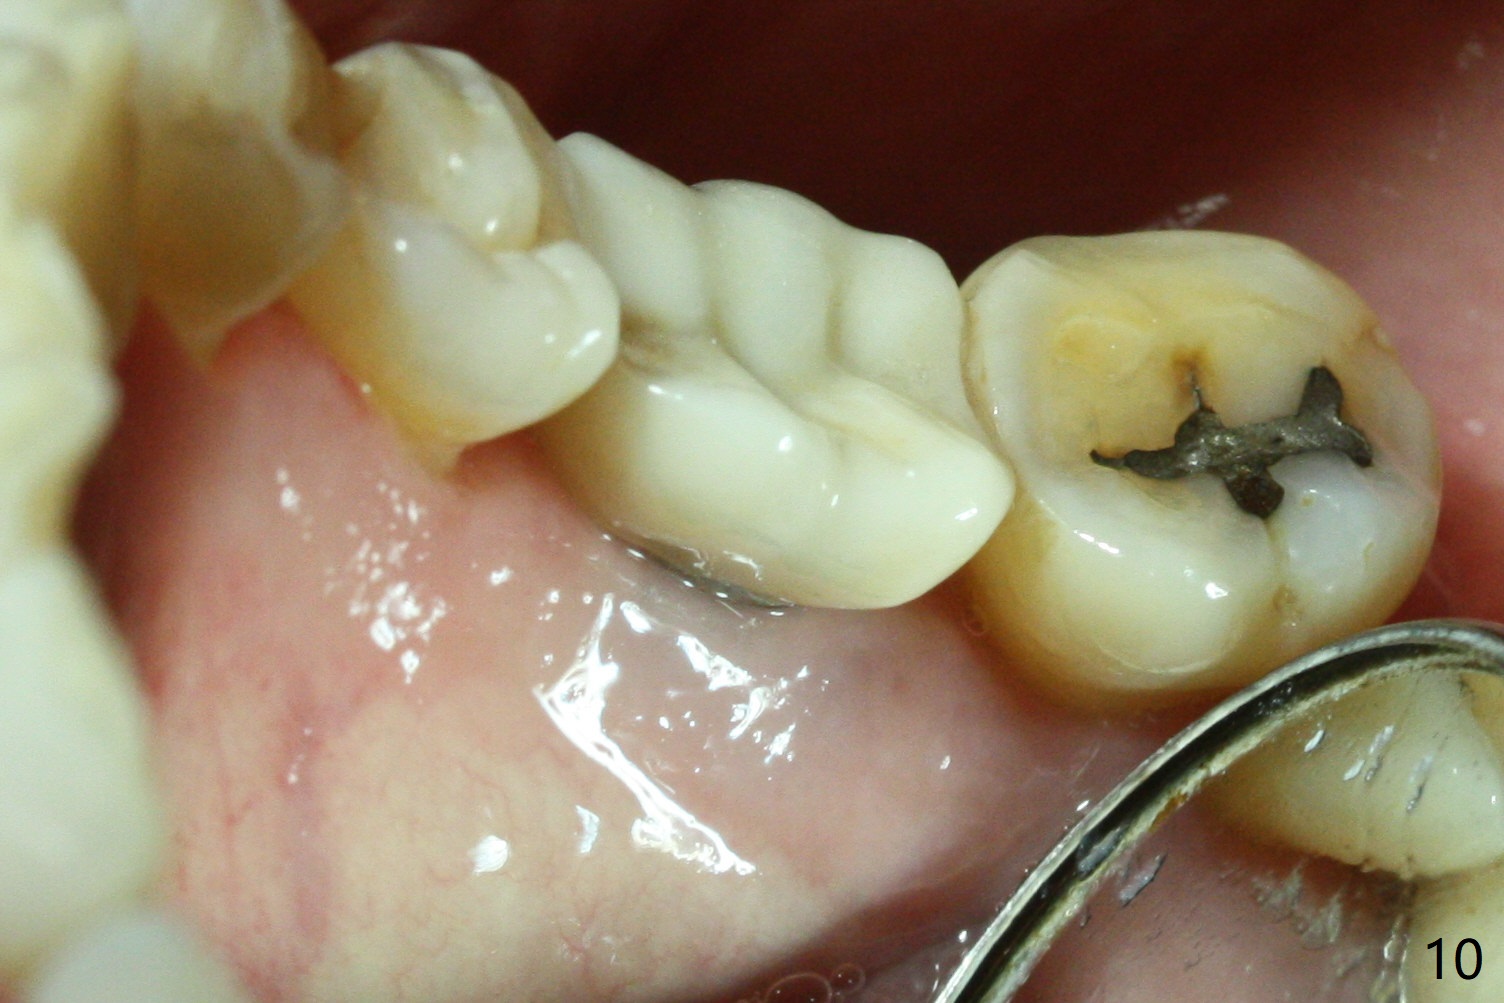

Upon flap reflection and granulation tissue curettage, the lingual threads are shown to be exposed with mesial bone resorption (Fig.5 <). The lingual defect is soaked with Clindamycin saturated gauzes (Fig.6 *), followed by copious irrigation, Emdogain application, bone graft and collagen dressing. The flap is sutured and covered by perio dressing.

There is no symptom or sign of periimplantitis 3 years 8 months post 2nd bone graft (Fig.7-10). However, the patient complains of gingival hemorrhage 8 months later (Fig.11,12 (buccal), 13 (lingual view)). Water Pik is recommended.